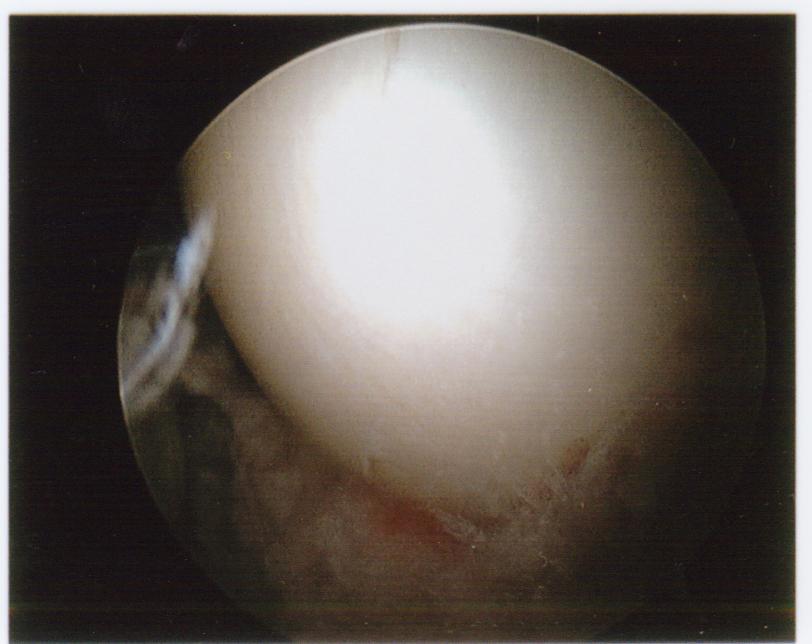

Move on if you’re squeamish. Otherwise, here are photos from my first arthroscopic hip surgery, in July 2011.